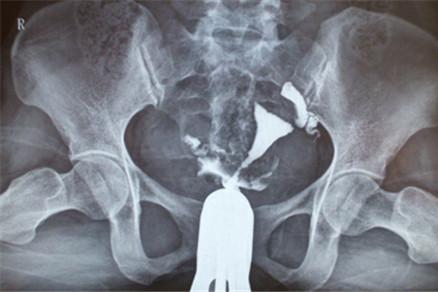

最常见的是B超,常表现为卵巢周围存在一些“腊肠”样的结构;

子宫输卵管造影也能发现输卵管积水;

最准确的要算腹腔镜或开腹手术,眼见为真,术中发现的输卵管积水那就是实实在在的积水